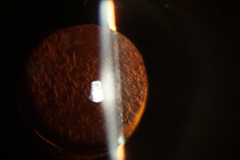

![]() 白內障 |

![]() 術後第一日 |